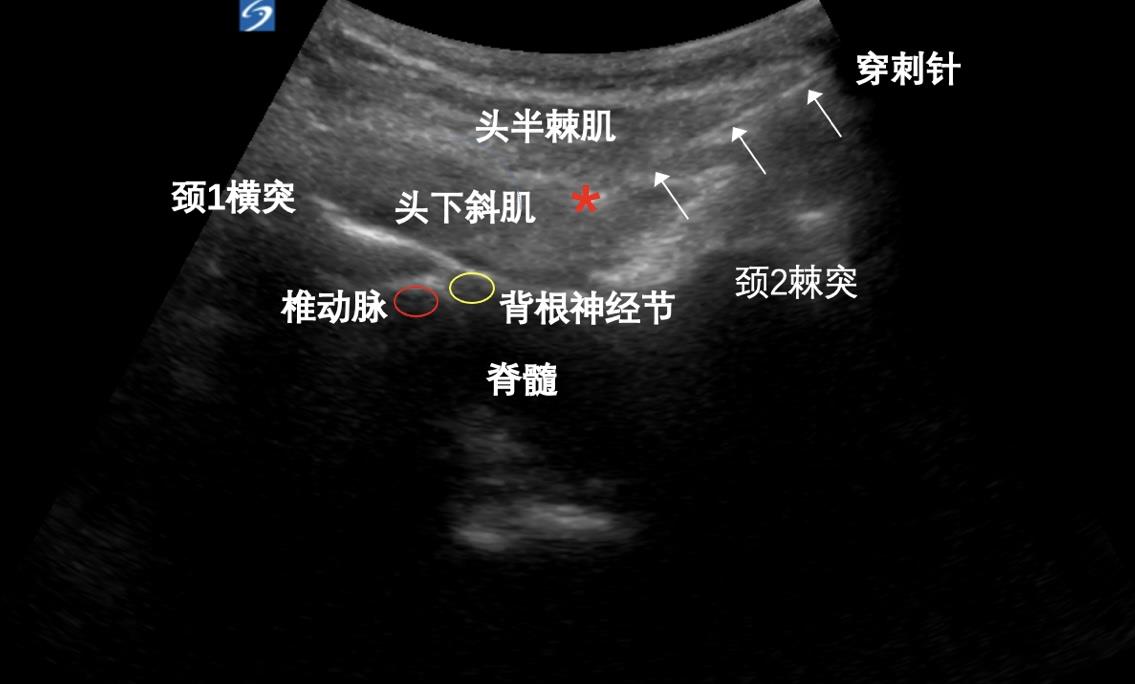

目的 比较低温等离子消融术与高电压长时程脉冲射频术治疗颈源性头痛(cervicogenic headache, CEH)的疗效和安全性。 方法 收集颈源性头痛患者80例,按照手术方式分为两组:低温等离子消融组(L组,n = 50);高电压长时程脉冲射频组(H组,n = 30)。L组采用颈脊神经后内侧支低温等离子消融术联合肌筋膜松解,H组采用颈脊神经后内侧支高电压长时程脉冲射频术联合肌筋膜松解。记录患者术前(T0)及术后1周(T1)、4周(T2)、12周(T3)、24周(T4)的视觉模拟评分(VAS评分)、颈部活动障碍评分(ROM评分)、术后疼痛缓解率以及术后并发症的发生率,比较两组之间的有效性和安全性。 结果 两组患者术后各时点的VAS评分、ROM评分均较T0下降,差异有统计学意义(P < 0.05);与L组相比,H组各时点的VAS评分均降低,差异有统计学意义(P < 0.05),H组各时点的ROM评分均降低,差异无统计学意义(P > 0.05),T4时点H组的有效率高于L组,差异有统计学意义(P < 0.05)。两组术后均有头皮麻木的情况,T3时点H组的麻木发生率稍高于L组,差异有统计学意义(P < 0.05)。 结论 低温等离子消融术和高电压长时程脉冲射频术治疗颈源性头痛均有效,安全性均较好,但高电压长时程脉冲射频术术后24周的疗效优于低温等离子消融术。

关键词: 颈源性头痛, 低温等离子消融术, 高电压长时程脉冲射频术, 超声引导

Objective To compare the short?term efficacy and safety of low temperature plasma radiofrequence ablation (LA) vs. high voltage long duration pulsed radiofrequency (HL?PRF) in the treatment of cervicogenic headache (CEH). Methods Eighty patients with cervicogenic headache were divided two groups: one treated with low temperature plasma radiofrequence ablation group as group L (n = 50) and the other treated with high voltage long duration pulsed radiofrequency group as group H (n = 30). The two groups were compared in terms of the score by the Visual Analog Scale, score by the Range of Motion Scale, postoperative pain relief rate, postoperative complication incidence, 1, 4, 12, and 24 weeks after the operation, as well as the therapeutic effectiveness and safety. Results Both groups showed significantly lower VAS and ROM scores after operation (P < 0.05). Compared with group L, group H had significantly lower VAS (all P < 0.05) but insignificantly lower ROM scores (all P > 0.05) at each time point. At T4, group H had significantly higher therapeutic effectiveness rate (P < 0.05) and higher incidence of scalp numbness at T3, as compared to group L (P < 0.05). Conclusion The low temperature plasma radiofrequency ablation and high voltage long duration pulsed radiofrequency both are effective and safe in the treatment of CEH, the latter approach can achieve better therapeutic effectiveness 24 weeks after the operation than the former.

Key words: Cervicogenic headache, Low temperature plasma radiofrequency ablation, High voltage long duration pulsed radiofrequency, Ultrasound guided